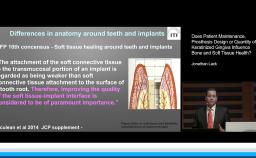

Patients with inadequate attached keratinized tissue often complain of pain and soreness when performing oral hygiene measures in comparison to patients with adequate keratinized tissue. Lack of keratinized tissue impedes proper oral hygiene leading to plaque accumulation, recession and compromised esthetics - even when patients present with good oral hygiene and are enrolled in a strict supportive and maintenance care program.

This presentation discusses recent studies showing that - although there are no minimum dimensional requirements - attached keratinized tissue is essential to facilitate oral hygiene measures and the long-term maintenance of implants.